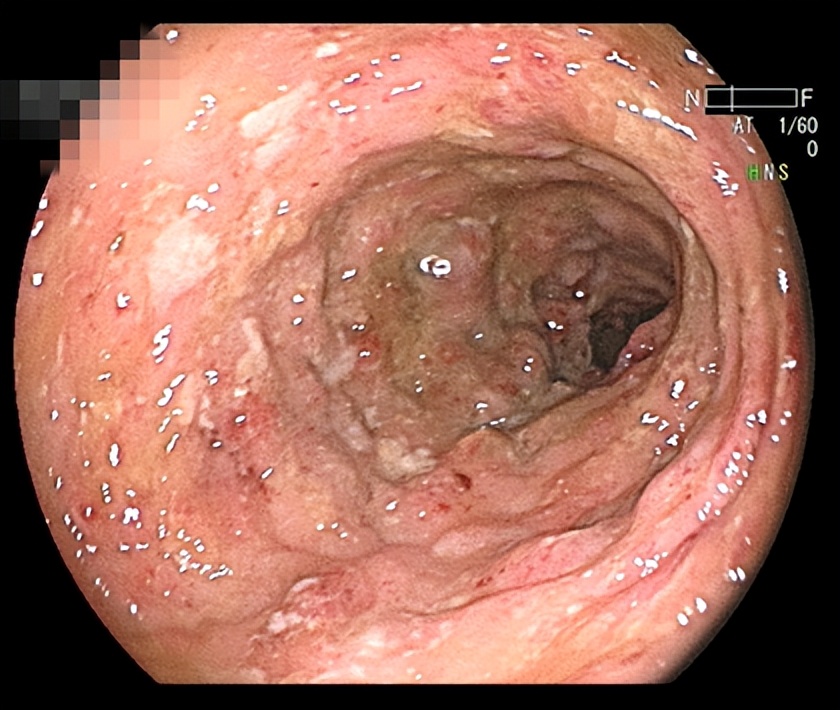

一个20多岁的年轻姑娘,很难想像她的肠道竟然是这样的:

据姑娘所述,她患有腹痛、腹泻、粘液脓血便,已经7、8年了,久治未愈,饱受折磨,甚至想做手术把坏掉的肠子切除。

经过检查,姑娘患有炎症性肠病,这种病很难根治,容易反复发作,需要长期用药,治疗效果不佳,严重影响患者生活质量,但因其没有典型的肿瘤结构,不会对寿命产生明显影响,故被称之为“绿色癌症”。